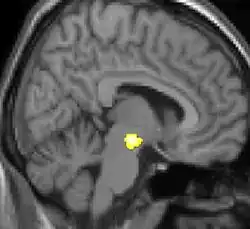

Neuro-imagerie

La morphométrie voxel par voxel (VBM) montre les différences structurelles des zones du cerveau

Les images par tomographie à émission de positron indiquent les régions du cerveau qui sont activées lors de la douleur, par rapport aux périodes sans douleur. Elles montrent les régions du cerveau qui sont toujours actives durant la douleur en jaune/orange (appelé "matrice-douleur"). La zone au centre (dans les trois vues) est spécifiquement activée uniquement pendant la crise. Les photos sur la ligne du bas (effectuées par VBM) montrent les différences structurelles entre les patients souffrant d'AVF et des personnes saines : seulement une partie de l'hypothalamus est différente[50],[51].

Il semble exister des anomalies microstructurales hypothalamiques bilatérales (en l'occurrence l'existence d'une hypertrophie)[52] sans que l'on sache si ces anomalies sont la cause ou la conséquence de la répétition des crises.